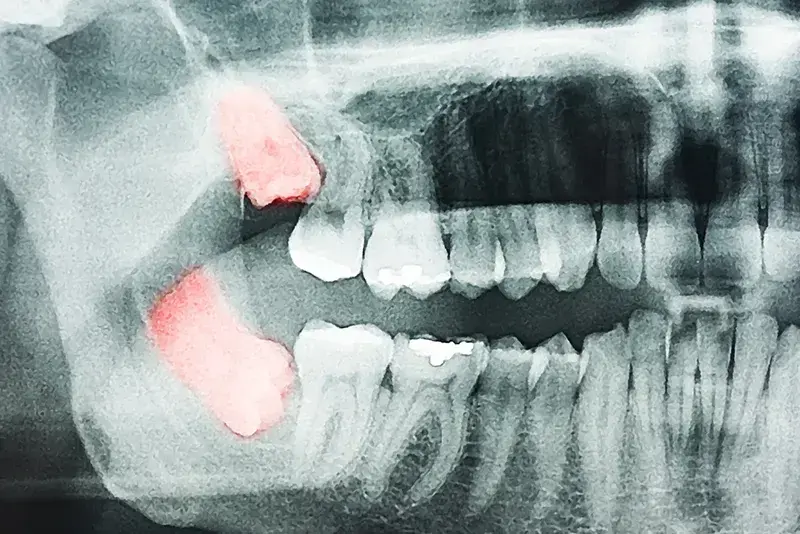

Dents de sagesse ou canines incluses

Il est fréquent de devoir surveiller les dents de sagesse car elles peuvent se présenter de manière inadéquate: soit incluses (elles n’ont pas la place de sortir et risquent de pousser d’autres dents), soit semi-incluses (elles ne ressortent que partiellement).

L’extraction des dents de sagesse n’est pas un fait rare. Et plus vite elles seront prises en charge, moins le risque de complications sera grand. C’est pour cela que nous recommandons de vérifier, dès l’adolescence, leur positionnement et d’anticiper leur trajectoire. Un contrôle une fois par an minimum est recommandé.